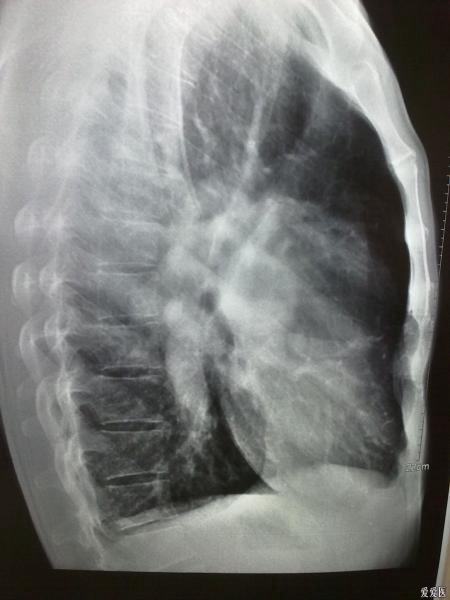

典型肺动脉高压胸片(室间隔缺损)

1、肺动脉段突出。2、肺血管纹理变少了。3、右心室大,心尖圆钝。。